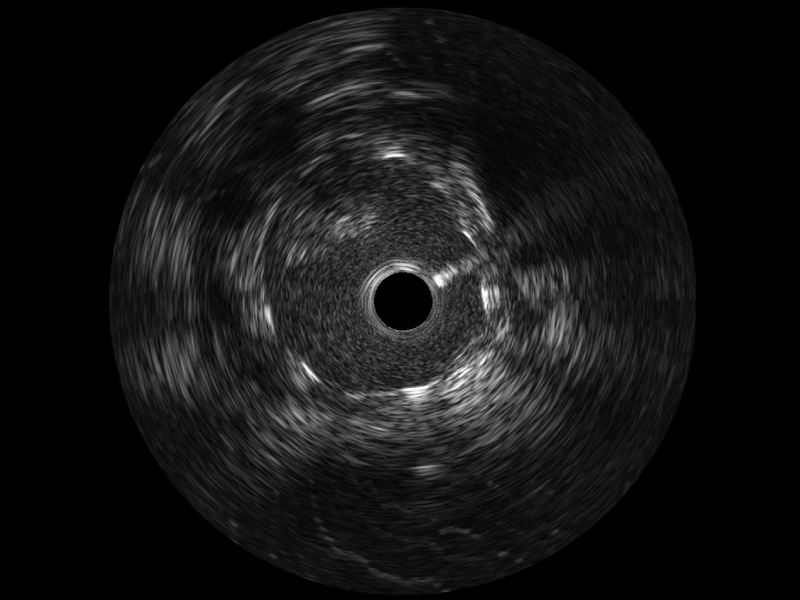

九州酷游宽频IVUS图像

对比传统IVUS导管成像,九州酷游宽频IVUS图像的近场支架梁显影更细腻,远场中膜外血管仍清晰可辨,兼顾远中近,兼顾分辨力与穿透深度